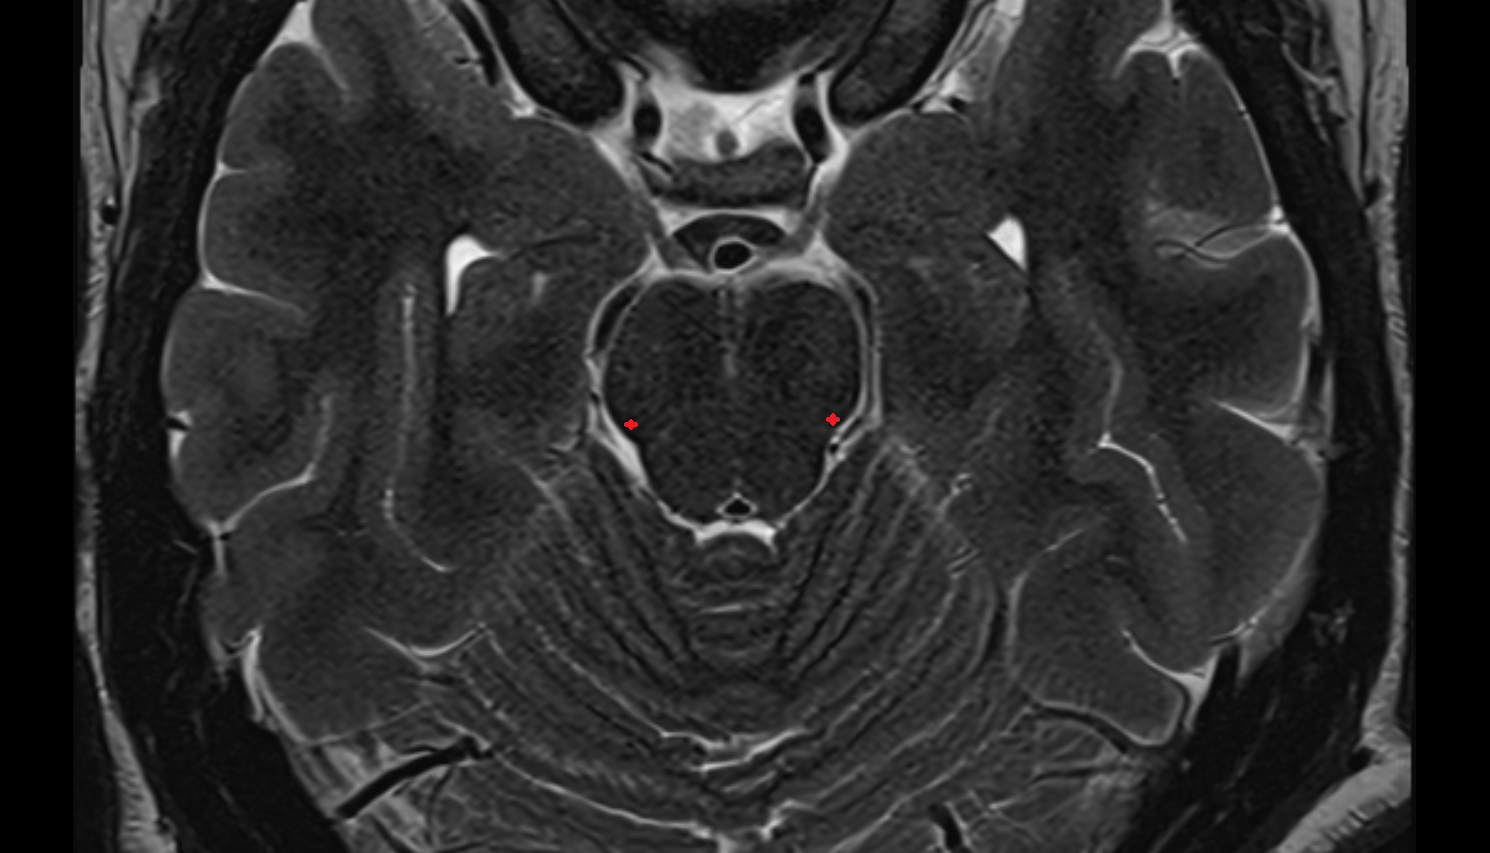

- Lateral aperture of fourth ventricle (foramen of Luschka)